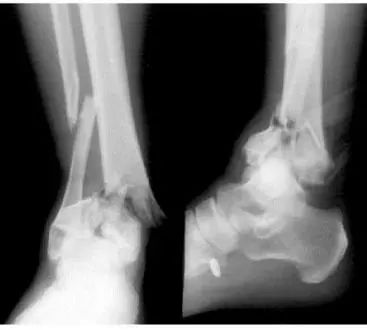

2)外固定支架跨踝关节固定限制了踝关节的活动,固定时间长后肯定会影响踝关节功能,因此术后6-8周,当骨折部位疼痛消失,复查X线片骨折线模糊时,可通过放松钢钉固定夹和万向节而减少固定程度,允许踝关节有少量活动,尽可能恢复踝关节功能。

3)要先良好的复位并固定腓骨。腓骨复位内固定对Pilon骨折的稳定有重要作用,而且腓骨的准确复位固定保证了踝关节的正常形态,对踝关节的正常功能起到重要作用,特别是Pilon骨折,胫骨难于固定,而且仅仅固定胫骨不能稳定踝关节和恢复踝关节解剖形态,这时腓骨的切开复位内固定更为重要。因此Pilon骨折的处理首先恢复腓骨的解剖对位和稳定性,恢复小腿长度,然后才能处理胫骨远端的粉碎骨折。

综上所述,外固定支架结合有限内固定治疗Pilon骨折是一种操作简单,创伤小,干扰局部组织血运较少,有利于伤口和骨折愈合,能早期踝关节活动,避免踝部关节炎的发生或延迟发生,最大程度恢复踝关节功能的手术方式。